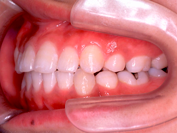

(注) この患者さんの治療の詳細は、院長の治療例の「叢生」(ここをクリック)で詳しく解説しておりますので、治療の方法や期間、治療費、リスク等はそちらを参照してください。